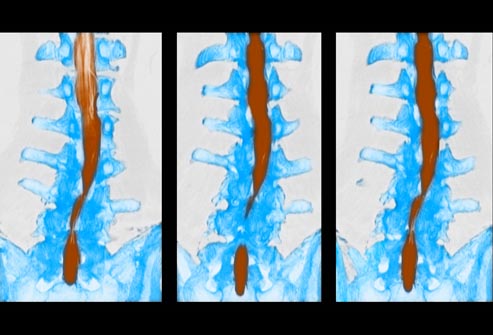

Diagnosing Low Back Pain

To help your doctor diagnose the source of low back pain, be specific in describing the type of pain, when it started, related symptoms, and any history of chronic conditions. Your doctor may order X-rays, CT or MRI scans to look for damaged bones or discs, or other injuries to the spine.

If long-lasting back pain is interfering with your daily life, and other treatments have not provided relief, you may be a candidate for surgery. Depending on the cause of your pain, a surgeon may remove a herniated disc, widen the space around the spinal cord, and/or fuse two spinal vertebrae together.